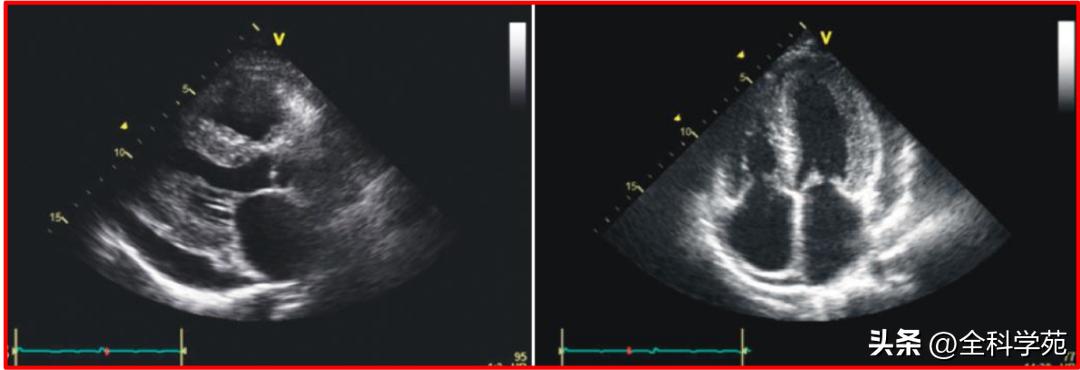

C:心脏彩超: 左心房、右心房增大, 左室射血分数(LVEF)40% ,左室壁厚度14mm,心肌回声不均匀,可见 细颗粒状回声 , 左右心室壁运动均减弱

D:心脏彩超:室间隔及左、右室壁厚度正常, 左室心尖部显示欠佳,可见不规则回声浸润心肌,分界不清 ,局部室壁运动大致正常